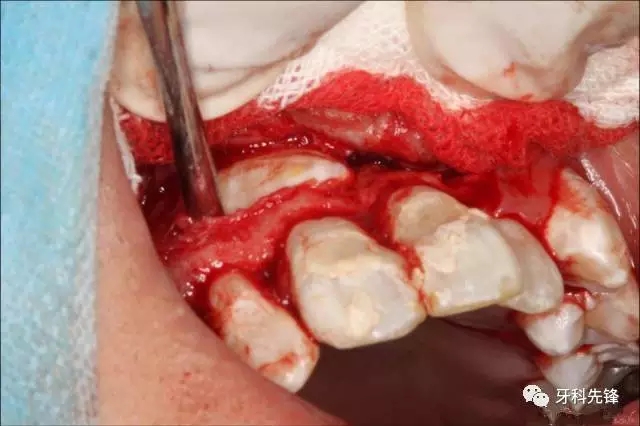

圖4.術(shù)前舌側(cè)觀,11、12舌側(cè)有開(kāi)髓孔,并有血性滲出

圖5.局麻下行唇側(cè)梯形切口